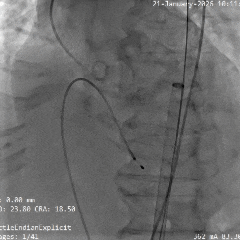

术中影像

双窦展开位根部造影

瓣叶狭窄明显,无明显反流

直头导丝顺利跨瓣

猪尾导管测量跨瓣压差约70mmHg

18mm球囊预扩,球囊上下滑动,无腰无漏,左冠显影,右冠无显影

输送系统顺利过弓

造影确认初始定位零位

瓣膜稳定展开

全展开位造影评估

瓣架呈直筒型,位置接近0位,少量反流

瓣膜缓慢脱钩,可见瓣膜实现自同轴,且无位移

脱钩后造影评估

瓣架形态佳位置可,冠脉显影,导丝压瓣可见反流

最终根部造影

撤出心室导丝后,反流明显减少